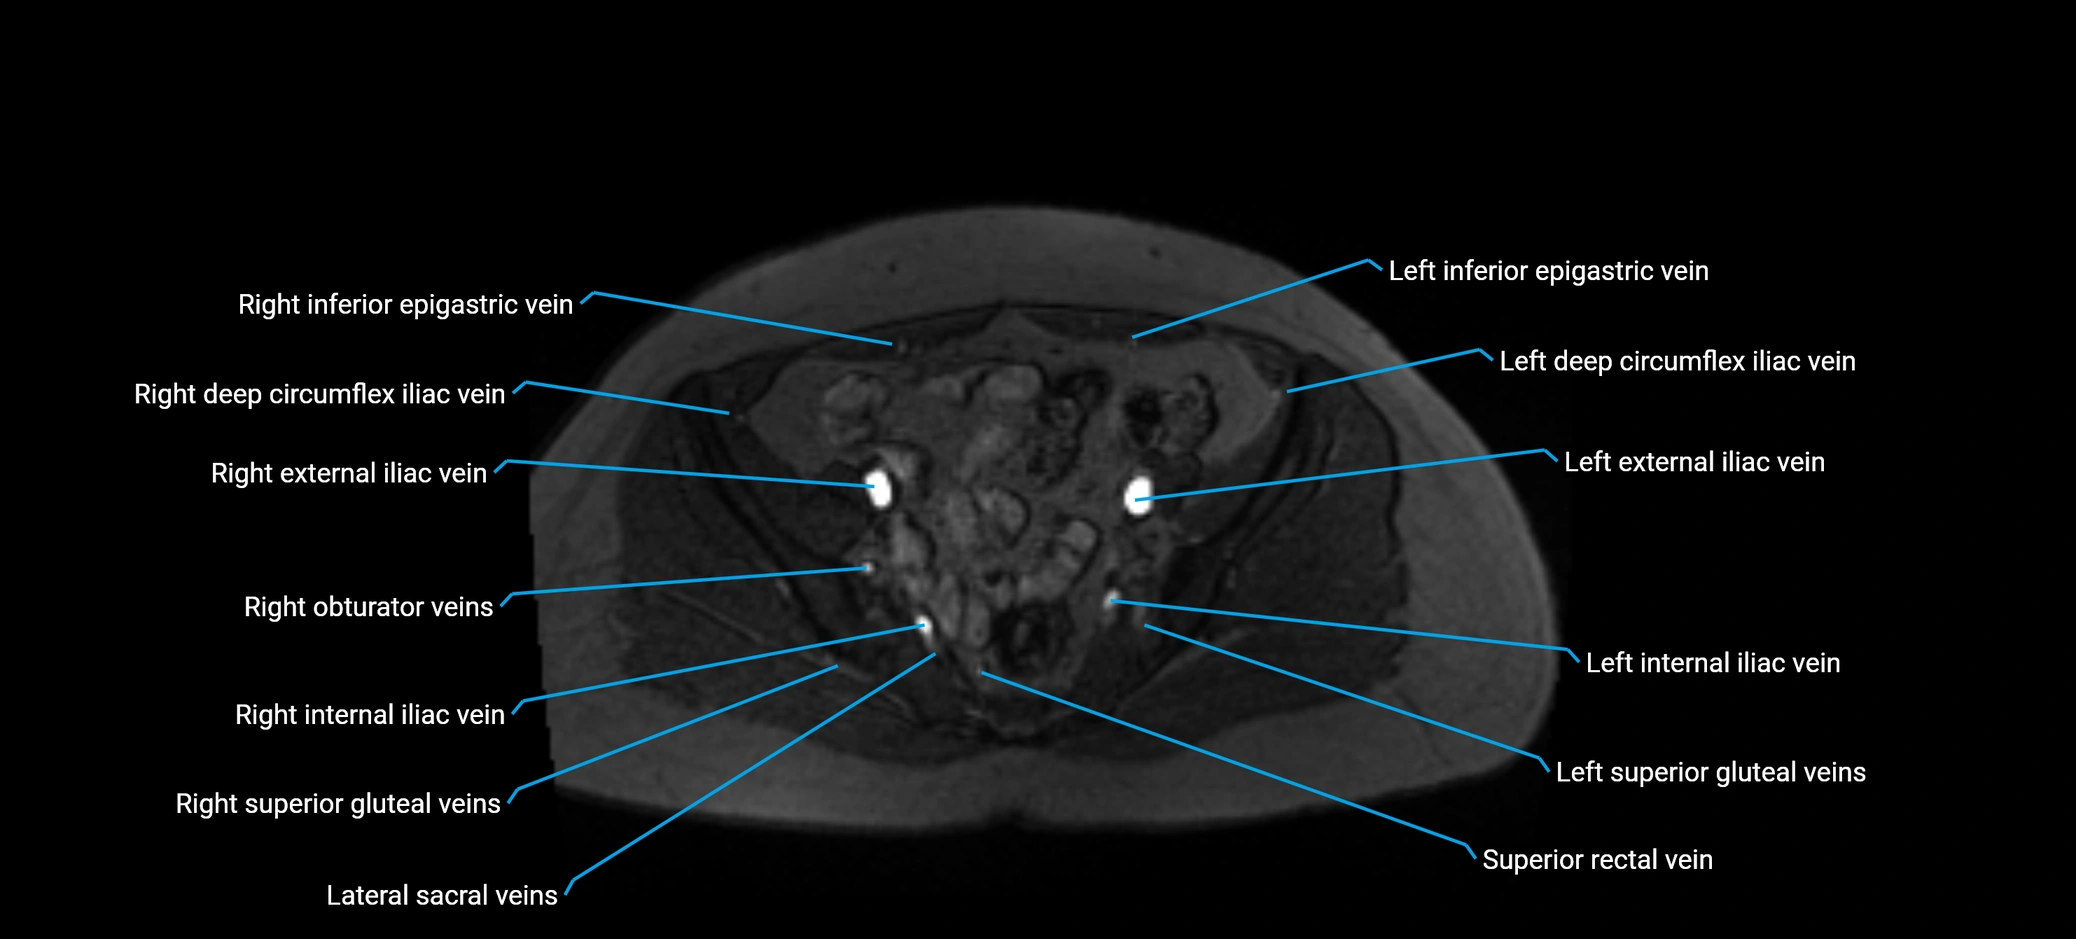

MRI image

image